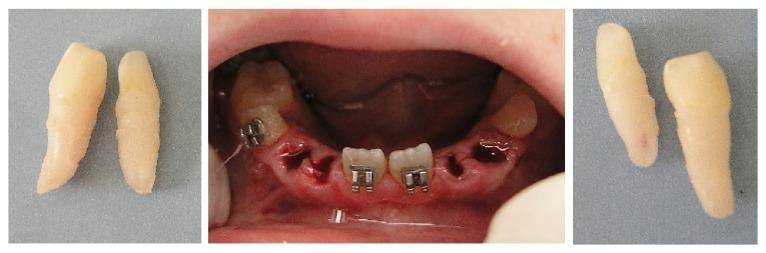

Bilateral mandibular tooth transposition is a relatively rare dental anomaly caused by distal migration of the mandibular lateral incisors and can be detected in the early mixed dentition by radiographic examination. Early diagnosis and interceptive intervention may reduce the risk of possible transposition between the mandibular canine and lateral incisor. This report illustrates the orthodontic management of bilateral mandibular canine-lateral incisor transposition. Correct positioning of the affected teeth was achieved on the left side while teeth on the right side were aligned in their transposed position. It demonstrates the outcome of good alignment of the teeth in the dental arch.

双侧下颌牙齿易位是一种相对罕见的牙齿异常,由下颌侧切牙向远中移位引起,可通过影像学检查在混合牙列早期发现。早期诊断和阻断性干预可能会降低下颌尖牙和侧切牙之间可能发生易位的风险。本报告阐述了双侧下颌尖牙-侧切牙易位的正畸治疗。左侧患牙实现了正确定位,而右侧牙齿则在其易位位置排齐。它展示了牙弓中牙齿良好排齐的效果。